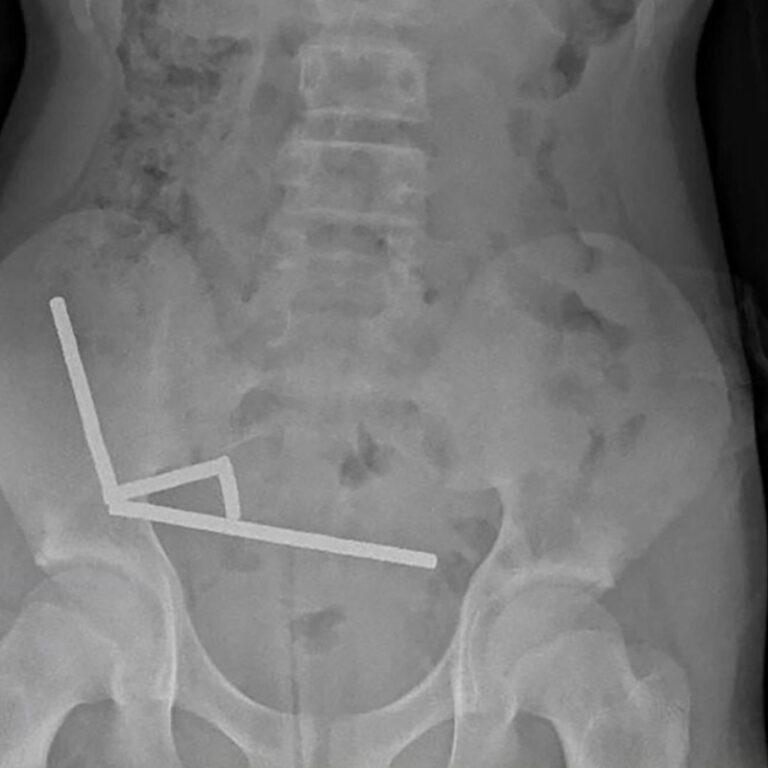

Η ακτινογραφία έδειξε ότι οι μαγνήτες είχαν συγκεντρωθεί σε τέσσερις ευθείες γραμμές μέσα στα έντερα του παιδιού, όπως φάνηκε και στην ακτινογραφία.

«Φαινόταν ότι βρίσκονταν σε διαφορετικά σημεία του εντέρου, τα οποία είχαν κολλήσει μεταξύ τους λόγω των μαγνητικών δυνάμεων», αναφέρει η έκθεση.